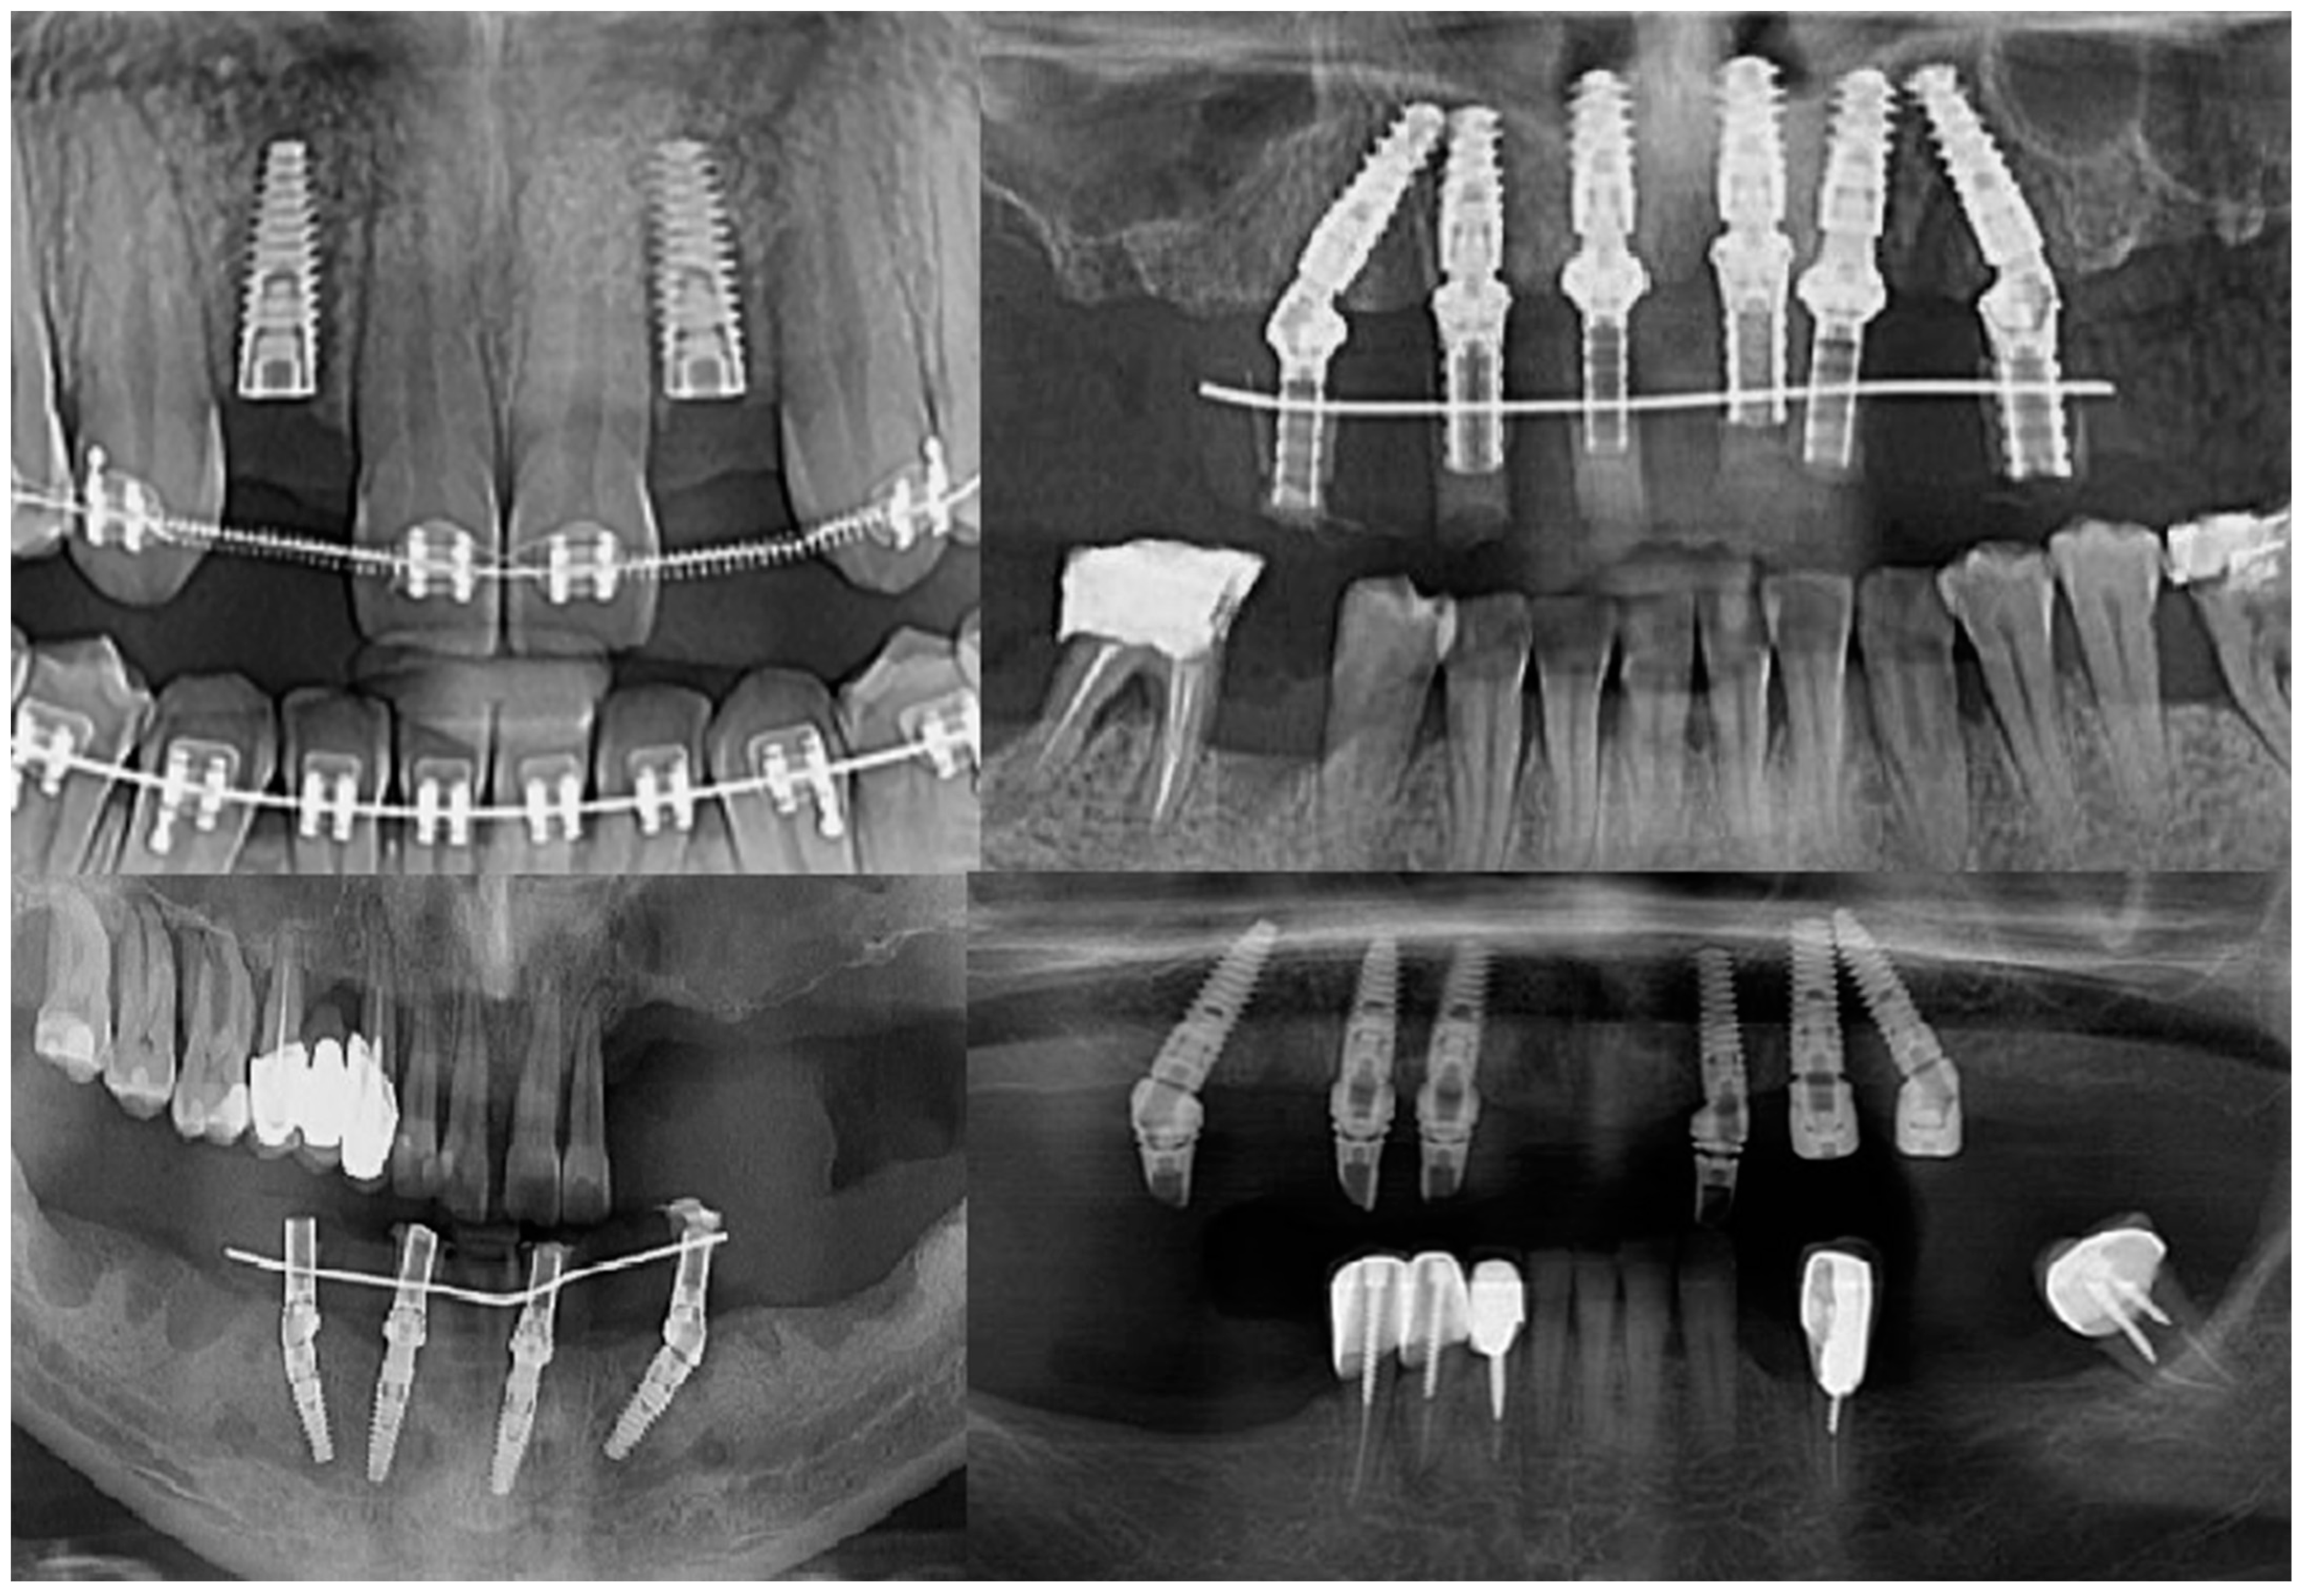

Intraoperatively, the dental implants were screwed into the alveolar bone according to the manufacturers’ indications, being applied over the dental implant with either a covering screw or healing abutment or multiunit abutment (Figure 1). The postoperative wound was sutured with Dafilon™ 4/0 suture thread (BBraun Hessen, Germany BBraun, Spangenberg, Germany) and Dafilon™ 5/0 suture thread (BBraun Hessen, Germany BBraun, Spangenberg, Germany).

Figure 1.

Radiological images presenting different clinical cases included in the study.